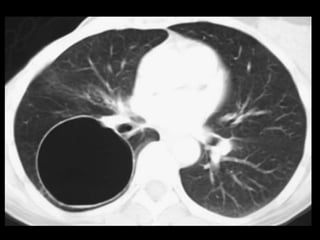

Mucormicose